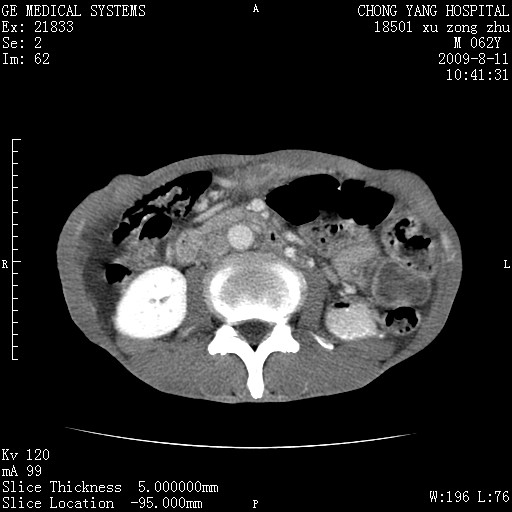

以下是引用杀毒软件在2009-8-11 16:35:00的发言:[br]肝内胆管扩张局限于左叶,胆管内有结石伴肝外胆管结石,胆管壁增厚呈弥漫性并发腹腔积液,胰腺边界模糊。[br][br]考虑---胆总管及肝内胆管结石继发胆管炎及胰腺炎,左肾下极囊肿,腹水。

以下是引用zjzjr在2009-8-11 17:35:00的发言:[br]肝内胆管扩张局限于左叶,胆管内有结石伴肝外胆管结石,胆管壁增厚呈弥漫性并发腹腔积液。[br][br]考虑---胆总管及肝内胆管结石继发胆管炎,左肾下极囊肿,腹水。